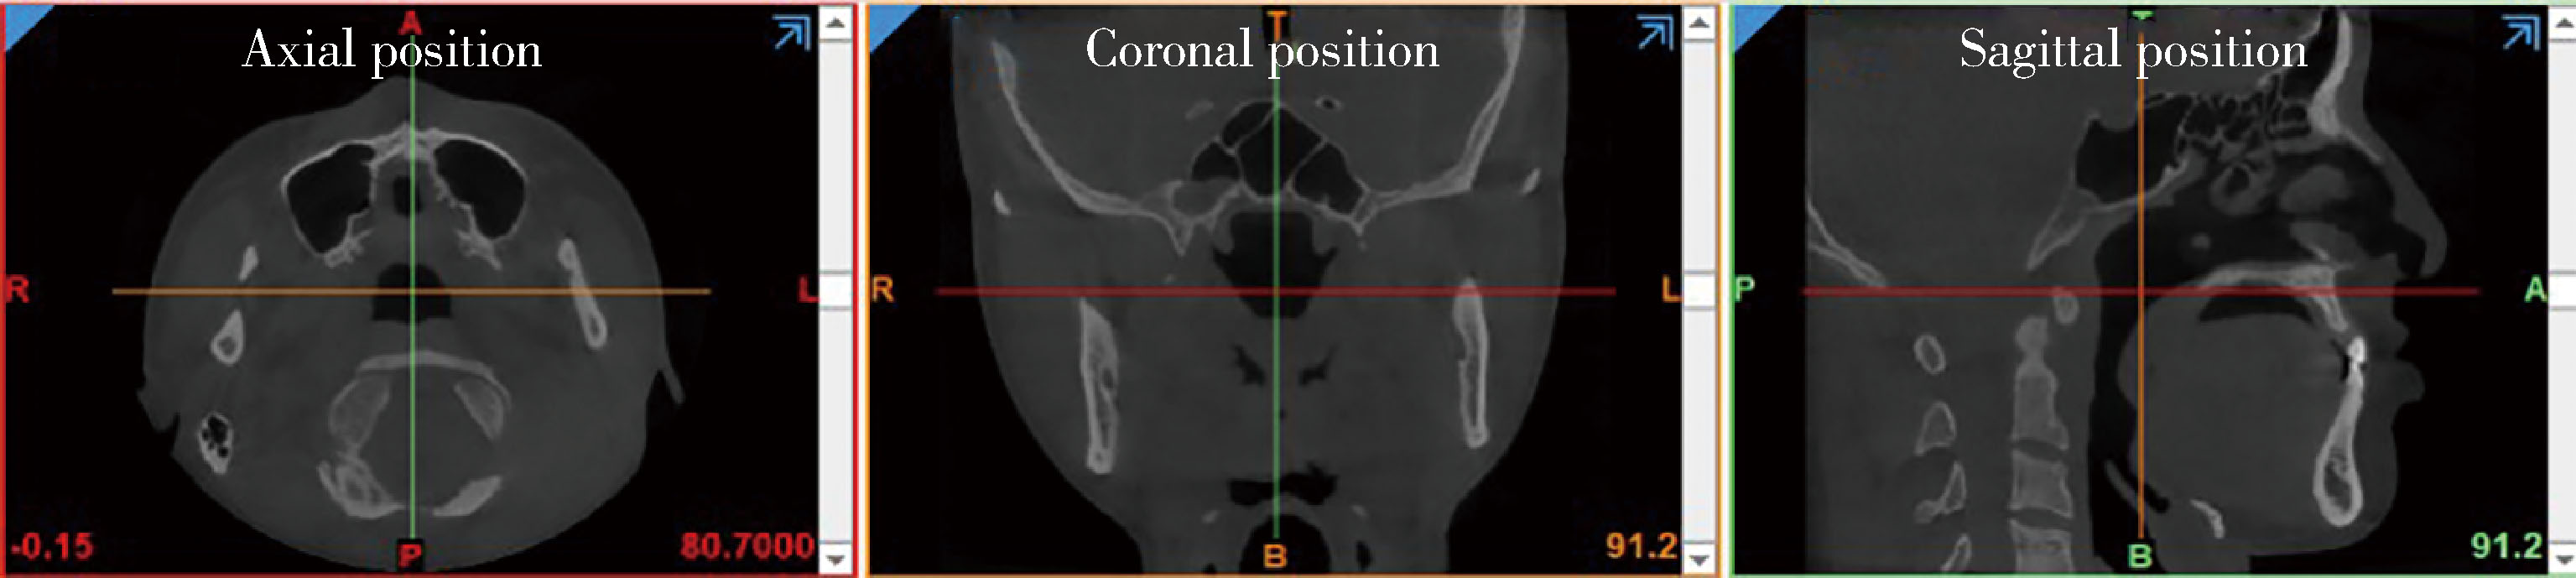

图1

锥形束CT图像"

目的: 建立下颌骨及乳牙缺失数字化丝圈间隙保持器的三维有限元模型,以探讨下颌第二乳磨牙缺失患者佩戴丝圈间隙保持器时的应力、变形及剪切力情况。方法: 通过对患儿进行锥形束CT(cone beam computed tomography,CBCT)扫描,使用Mimics 21.0软件建立下颌第二乳磨牙缺失的数字模型。利用儿童丝圈间隙保持器设计软件构建冠部固位与丝圈结构一体化的全冠及带环丝圈间隙保持器的数字模型,并分别采用钴铬合金、聚醚醚酮(polyether ether ketone,PEEK)及钛合金三种材料进行构建。在ANSYS Work Beach 2023 R2软件中,对模型46和84的咬合面施加垂直和沿牙体长轴倾斜45°的70 N载荷,以及丝圈上表面10 N载荷,模拟患儿佩戴丝圈间隙保持器时的正中咬合与侧方咬合,分析丝圈间隙保持器及基牙的受力情况。结果: 在不同的加载条件下,带环丝圈间隙保持器的最大主应力明显低于全冠丝圈间隙保持器。应力云图显示,最大主应力峰值出现在丝圈末端与冠部结构连接处,表明这一部位更容易发生断裂;使用PEEK材料制作的带环丝圈间隙保持器内部组织面的最大剪切应力最小;46和84牙齿的等效应力(Von Mises应力)最小,分别为23.18 MPa和36.35 MPa,且最大等效应力分别位于46牙齿近中、84牙齿远中靠近牙根部与丝圈间隙保持器接触的区域。结论: 在第二乳磨牙缺失的情况下,佩戴数字化带环丝圈间隙保持器能够有效分散应力,且PEEK材料的带环丝圈间隙保持器在一定程度上降低了基牙的受力,其在临床应用中显示出一定的优越性。

Objective: To establish a three-dimensional finite element model of a digital wire loop space maintainer for the mandible and primary tooth loss, in order to investigate the stress, deformation, and shear force experienced by patients with the loss of the second primary molar when wearing the wire loop space maintainer. Methods: Cone beam computed tomography (CBCT) scans were performed on the patients to create a digital model of the mandible with the absence of the second primary molar using Mimics 21.0 software. A digital model integrating the crown's retention and the wire loop structure of the full crown and ring wire loop space maintainer was constructed using pediatric space maintainer design software, utilizing three different materials: cobalt-chromium alloy, polyether ether ketone (PEEK), and titanium alloy. In ANSYS Work Beach 2023 R2 software, vertical loads of 70 N, tilted 45° along the long axis of the tooth loads of 70 N, and a 10 N load on the surface of the wire loop were applied to the occlusal surfaces of models 46 and 84, simulating centric and lateral occlusions during chewing with the wire loop space maintainer in place. The stress states of the wire loop space maintainer and supporting teeth were analyzed. Results: Under various loading conditions, the maximum principal stress of the ring wire loop space maintainer was significantly lower than that of the full crown. Stress contour maps indicated that the peak of the maximum principal stress occurred at the junction of the wire loop and crown structure, indicating that this area was more susceptible to fracture. The ring wire loop space maintainer made from PEEK material exhibited the lowest maximum shear stress on the internal organizational surfaces, with equivalent stresses of 23.18 MPa and 36.35 MPa for models 46 and 84, respectively. Stress contour maps demonstrated that the maximum stress on tooth 46 was located at its mesial, while the maximum stress on tooth 84 was situated near the root area on its distal, in contact with the wire loop space maintainer. Conclusion: In cases of second primary molar loss, wearing the digital ring wire loop space maintainer can effectively distribute stress, and the ring wire loop space maintainer made from PEEK material reduces the stress experienced by supporting teeth to some extent, demonstrating its superiority in clinical application.